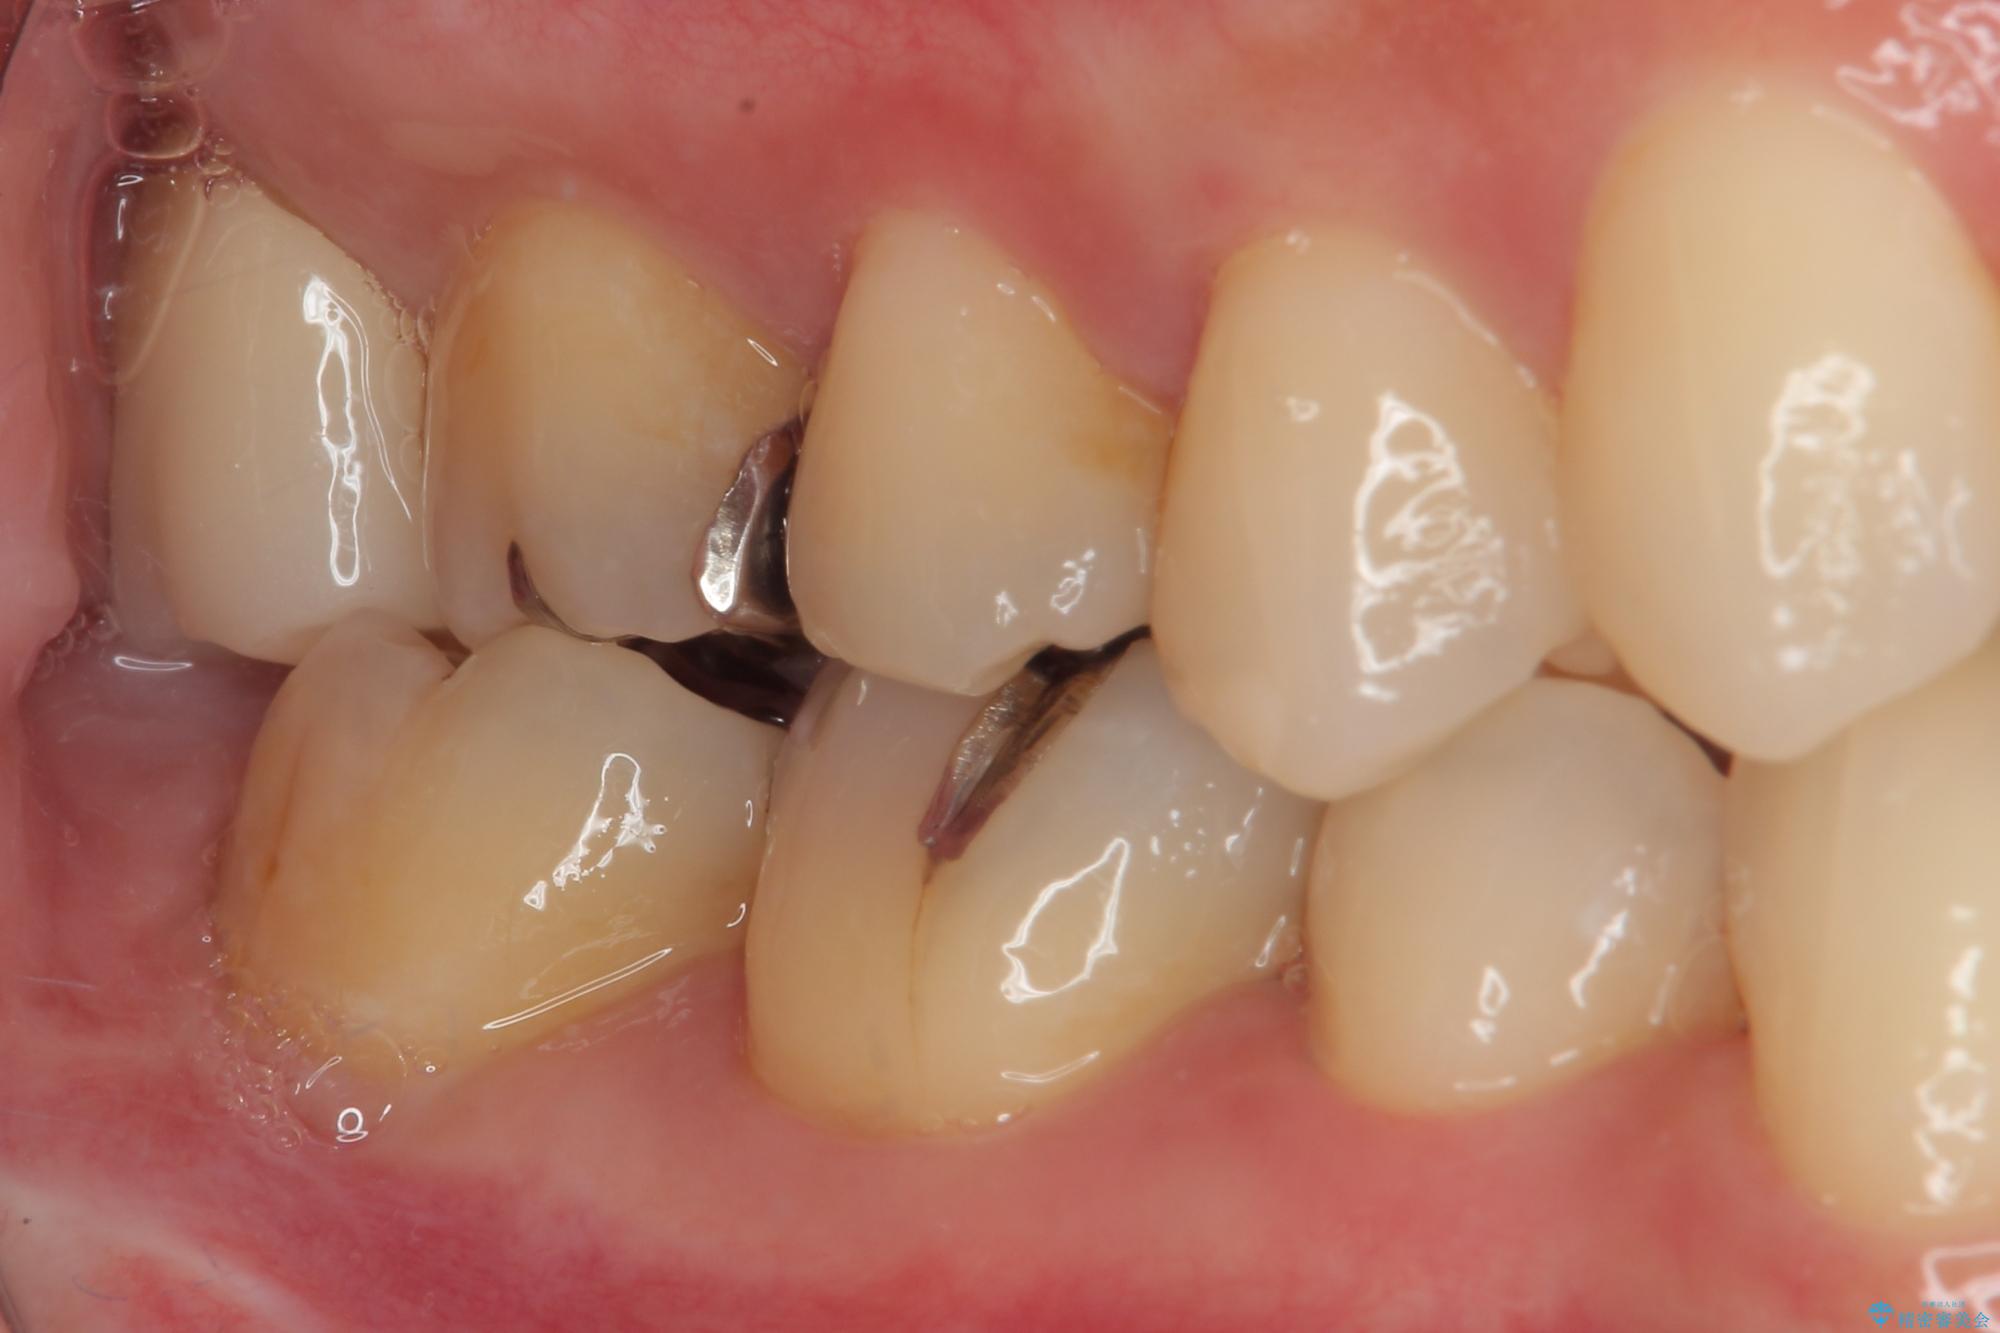

- 元々むし歯があったものの、処置が困難とのことでしたが、矯正治療を終えたので処置をしたいとのことで来院された患者様です。

左右ともに最後臼歯が頬側に顕著に突出しており、むし歯になってしまったことが想像されました。

矯正治療により処置が可能な位置に歯が移動したため、オールセラミッククラウンにて補綴治療を行うこととしました。

歯列が移動したとはいえ、左右ともに後方傾斜しており、むし歯の除去、形成(形を整える)、型取りの全てが非常に困難な処置となりました。